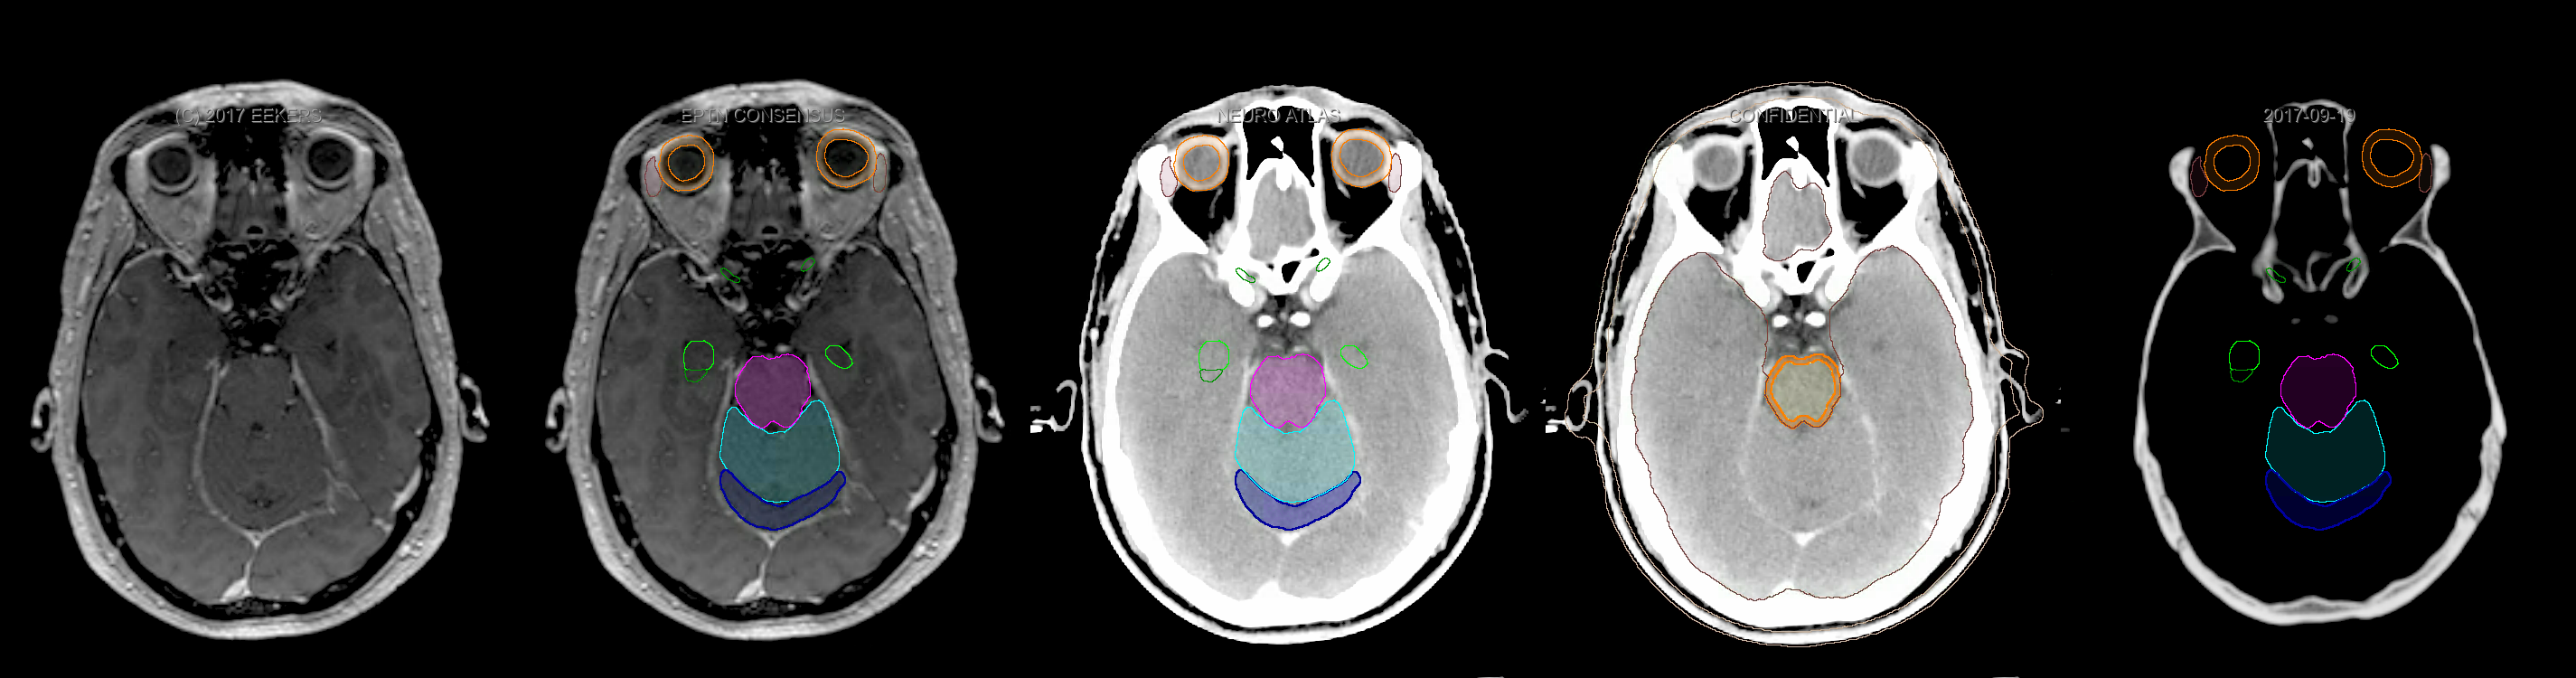

Three-dimensional delineation of the fifteen consensus OARs for neuro-oncology are shown on CT and 3 Tesla (3T) MR images (slice thickness 1 mm with intravenous contrast agent). All are presented in transversal, sagittal and coronal view.

From left to right: MR without structures, MR with structures, CT (WW/WL 120/40) with structures, CT (WW/WL 120/40) with Brain and Brainstem Surface, CT (WW/WL 1500/120)with structures